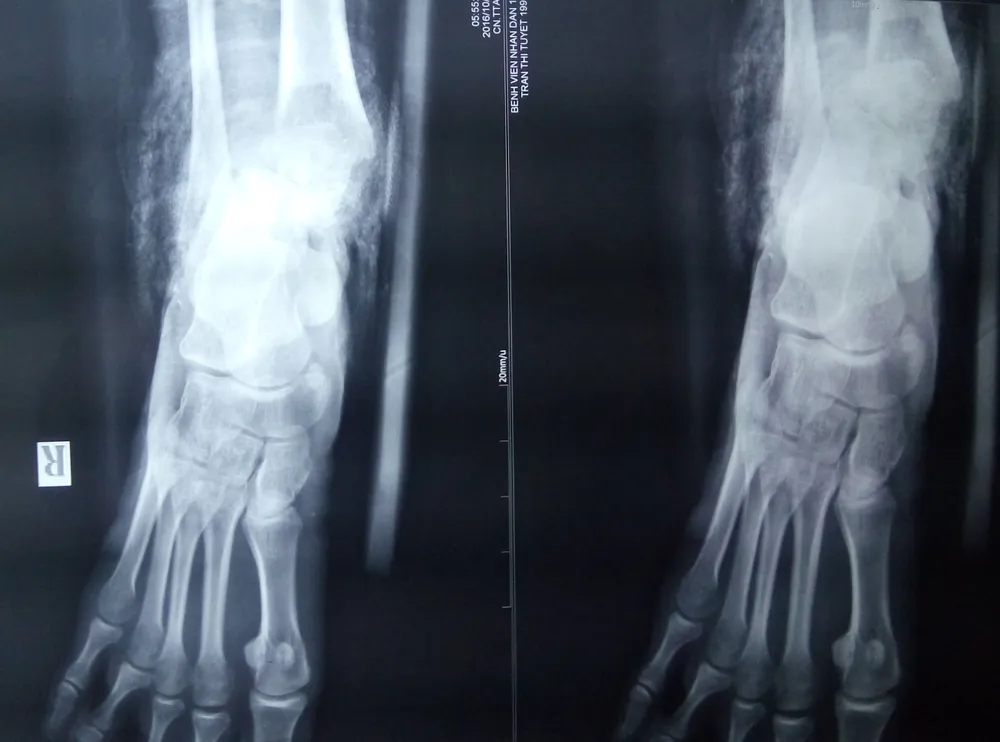

Kết quả chụp X quang cho thấy vùng cổ chân phải ông H bị nát toàn bộ. Ảnh: CAO VIỄN

Trước đó, ông H nhập BV Nhân dân 115 trong tình trạng nát toàn bộ vùng cổ chân phải, mất hết mạch máu nuôi dưỡng phần bàn chân. Vết thương quá nặng khiến xương cổ chân lòi ra ngoài. Ông H cho biết hiện là công nhân của một công ty trên địa bàn quận 10, TP.HCM. Trong lúc làm việc, do bất cẩn nên bị xe nâng hàng cán qua bàn chân.